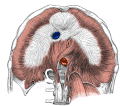

muscles of the human torso

Media in category "Muscles of the human torso"

The following 90 files are in this category, out of 90 total.